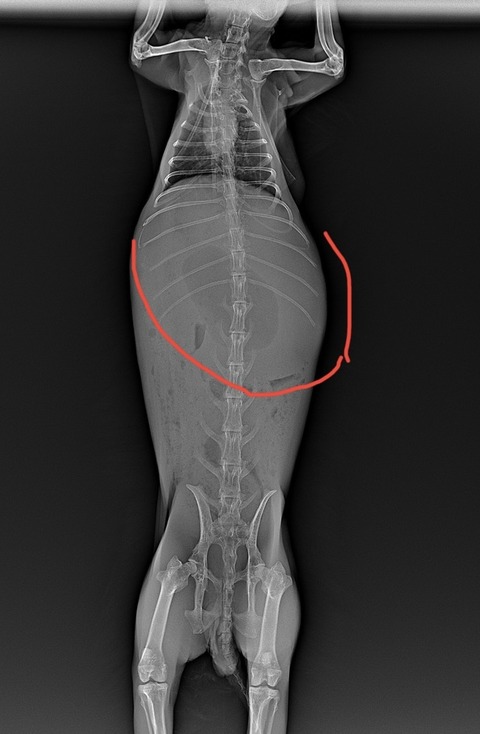

⇩異常な量の消化管ガス貯留が見られた症例

⇩巨大な膀胱結石が見られた症例

診断は触診、レントゲンで行います

胃は正常であれば、最後肋骨を少し越えるか越えないかくらいの大きさです

(⇩正常なサイズの胃)

胃拡張になると、最後肋骨を大きく越えてきます

(⇩急性胃拡張)

重篤なものほど、胃を触った時に硬結感がある時が多いように思います(私見)